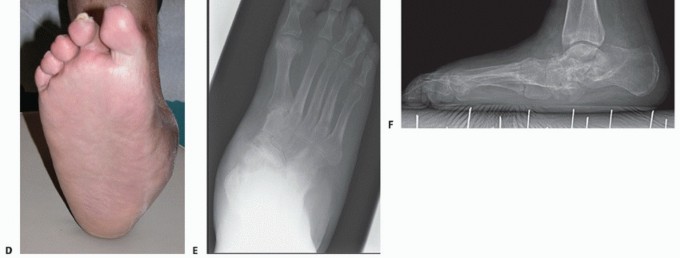

FIG 3 • A,B. Weight-bearing photographs of a 55-year-old diabetic male of normal body size. FIG 3B demonstrates that he is clinically plantigrade, that is, he is bearing weight on plantar skin designed for weight bearing. C. Weight-bearing anteroposterior radiograph demonstrating a relatively colinear talar-first metatarsal axis. Patients who are clinically and radiographically plantigrade are unlikely to develop tissue breakdown and can be managed longitudinally with therapeutic footwear. D,E. Clinical photographs 2 years following clinical presentation with active Charcot arthropathy. The foot is clinically plantigrade and capable of being managed longitudinally with commercially available therapeutic footwear (depth-inlay shoes) with custom accommodative foot orthoses. F. Weightbearing radiograph at follow-up. Although the radiograph demonstrates progression of the deformity between hindfoot and forefoot, the foot remained clinically plantigrade and has been successfully managed with commercially available therapeutic footwear.

Patients who are clinically and radiographically plantigrade can be treated with a weight-bearing total contact

cast during the active phase of the disease process.5,21 The cast should be changed every 2 weeks until the volume of the limb stabilizes and the foot is sufficiently stable to transition to therapeutic footwear (FIG 3).5,21